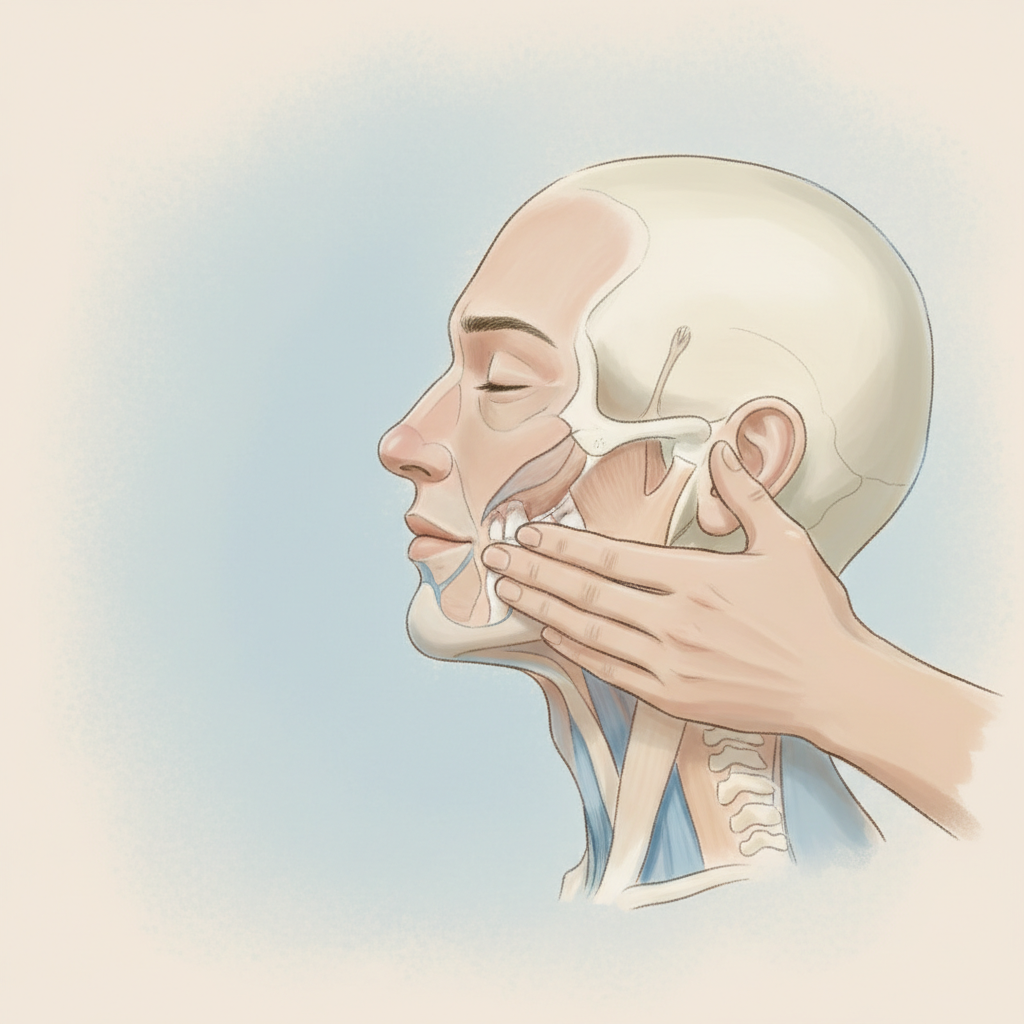

AGM Fisioterapia es la referencia en Oleiros para diagnóstico con ecografía y tratamientos invasivos mínimamente invasivos. Especializados en tendinopatías crónicas, lesiones deportivas, dolor de hombro, fascitis plantar y espolón calcáneo. Aplicamos EPI ecoguiada y ondas de choque focalizadas — técnicas que requieren formación específica y acceso a ecógrafo de alta resolución.